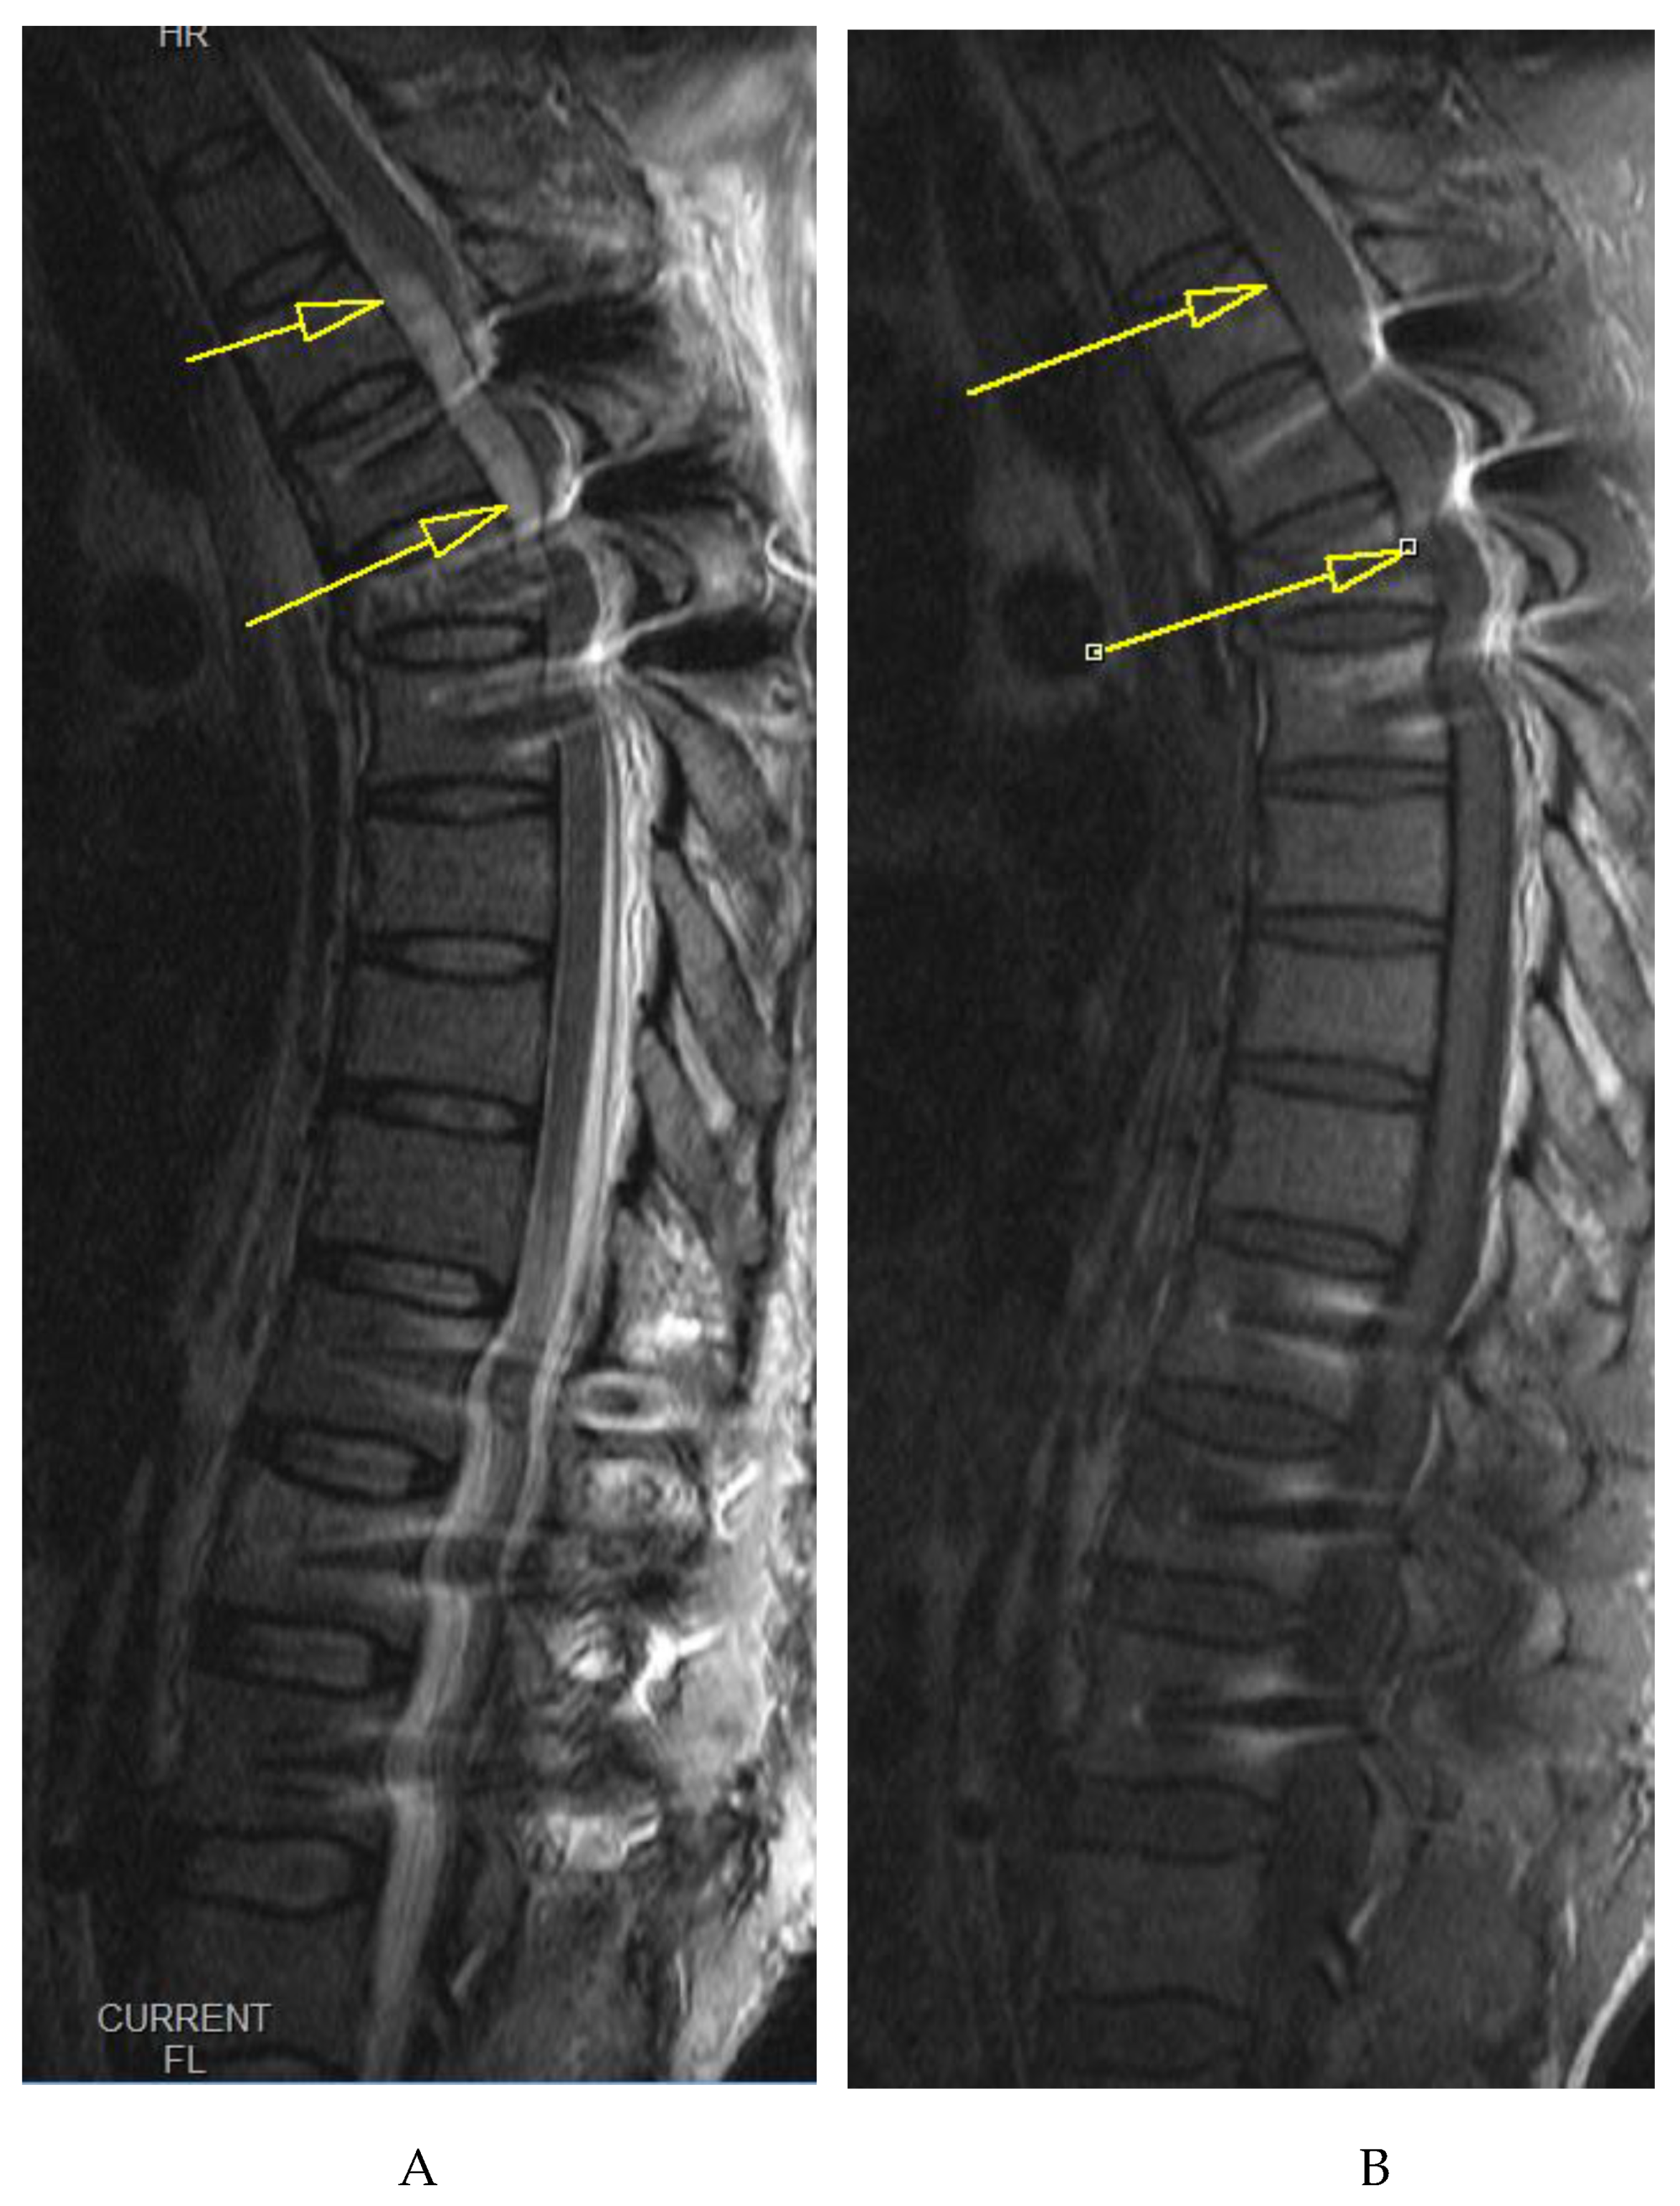

Normal bladder function was restored 2 days after surgery. Repeat MRI evaluation was done on 3rd postoperative day demonstrating significant resolution of hematoma as shown in Figure 5, and Figure 6. The subsequent hospital stay was uneventful. The patient was mobilized the day after surgery, pain medication tapered in 2 days, the wound healed primarily without signs of inflammation or dehiscence, and he is fully independent of daily tasks that do not require much stress on the spine.

Figure 5. Follow-up midsagittal views of T2 weighted (A) and T1 weighted (B) MRI images taken 3 days after initial emergency MRI showing significant resolution of the hematoma, measuring 2mm at its thickest.